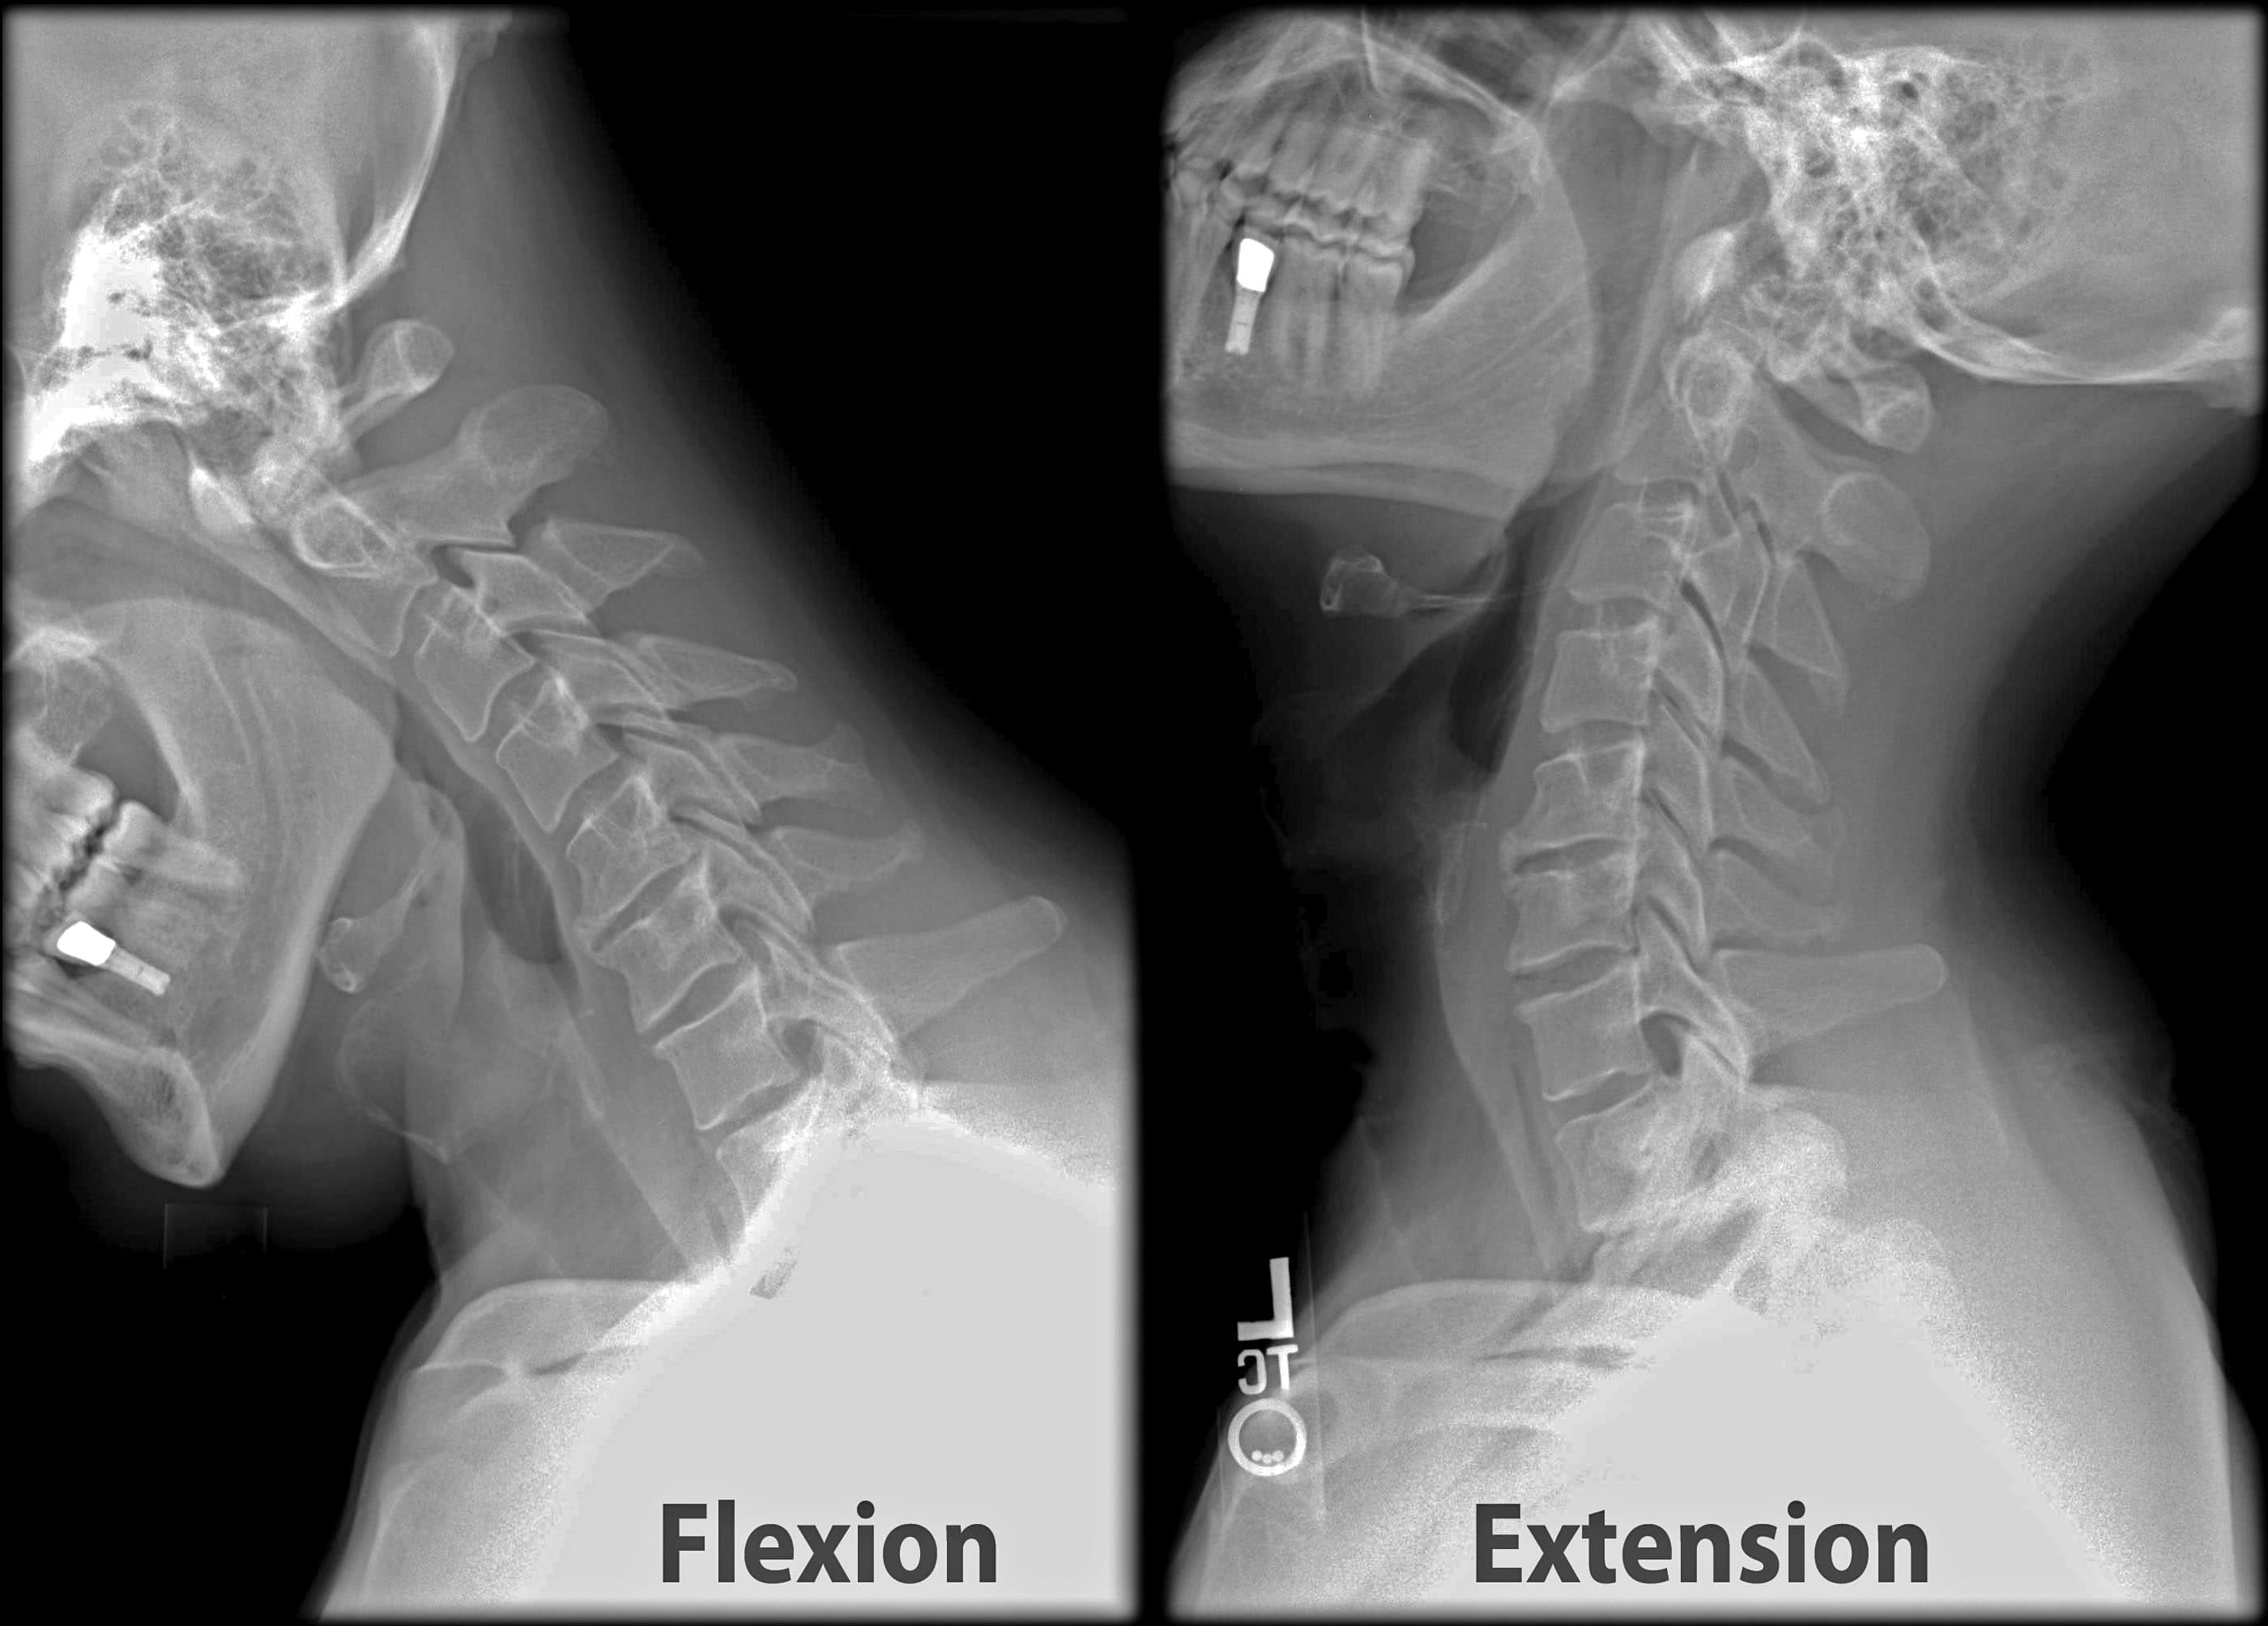

Here is a closer look at the most common goals and therapeutic activities used in neck injury rehabilitation when patients are still in the initial, most acute stages of their recovery. This information is followed by a review of specific exercises used to help all neck injury patients regain better ROM (range of motion), while lessening their pain and other difficulties.